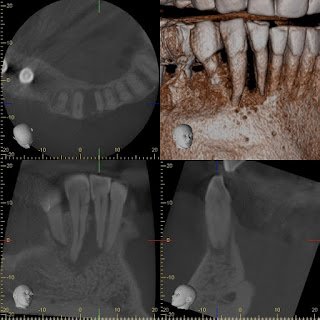

CBCT shows the apical and lateral bone loss on #26 and #27. The lateral bone loss on #27 is also suggestive of a possible root fracture, but since the tooth is necrotic, radiographic appearance alone is not enough evidence to diagnose this with a root fracture. CBCT also shows a 2 canaled root form on #26.